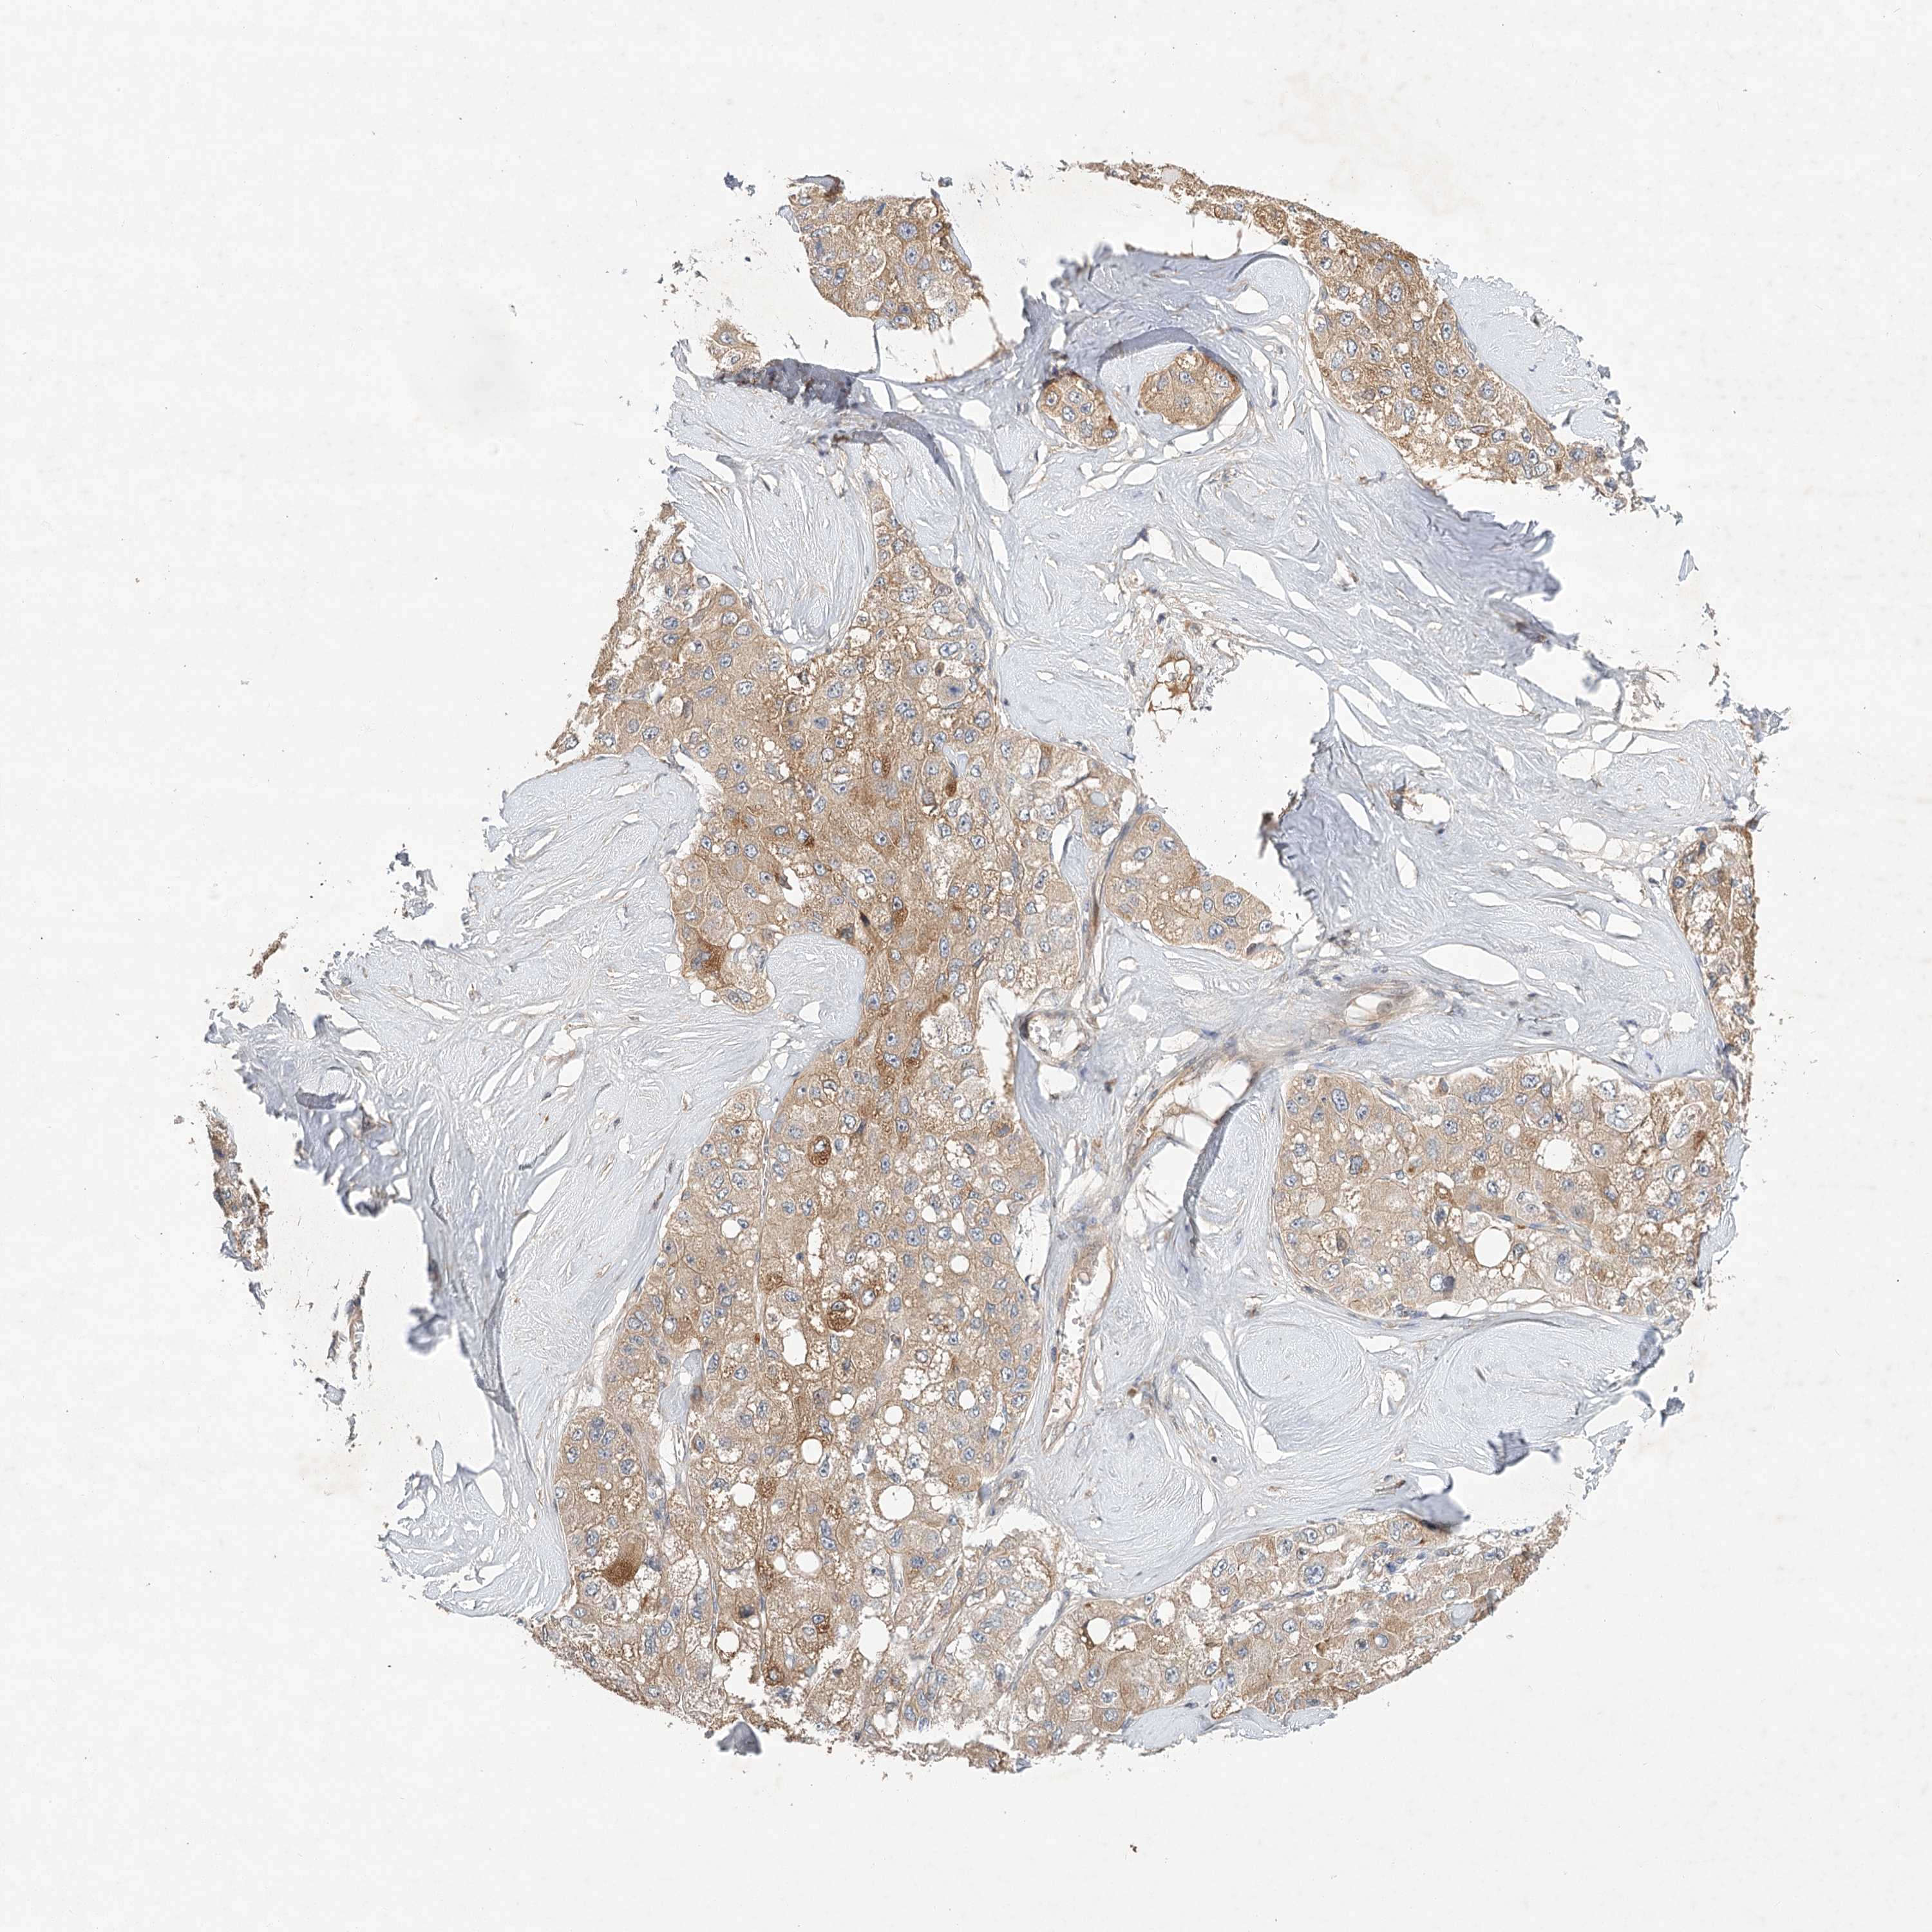

LIVER CANCER - Protein expressioni

A mouse-over function shows sample information and annotation data. Click on an image to view it in a full screen mode. Samples can be filtered based on level of antibody staining by selecting one or several of the following categories: high, medium, low and not detected. The assay and annotation is described here.

Note that samples used for immunohistochemistry by the Human Protein Atlas do not correspond to samples in the TCGA dataset.

Antibody stainingi

Antibody staining in the annotated cell types in the current human tissue is reported as not detected, low, medium, or high, based on conventional immunohistochemistry profiling in selected tissues. This score is based on the combination of the staining intensity and fraction of stained cells.

Each image is clickable and will lead to virtual microscopy that enables deeper exploration of all samples and also displays staining intensity scores, fraction scores and subcellular localization as well as patient and tissue information for each sample.

Antibody HPA032060

Antibody HPA032062

Antibody CAB034116

Staining

High

Medium

Low

Not detected

Intensity

Strong

Moderate

Weak

Negative

Quantity

>75%

75%-25%

<25%

None

Location

Nuclear

Cytoplasmic/membranous

Cytoplasmic/membranous,nuclear

Cholangiocarcinoma

Carcinoma, Hepatocellular, NOS